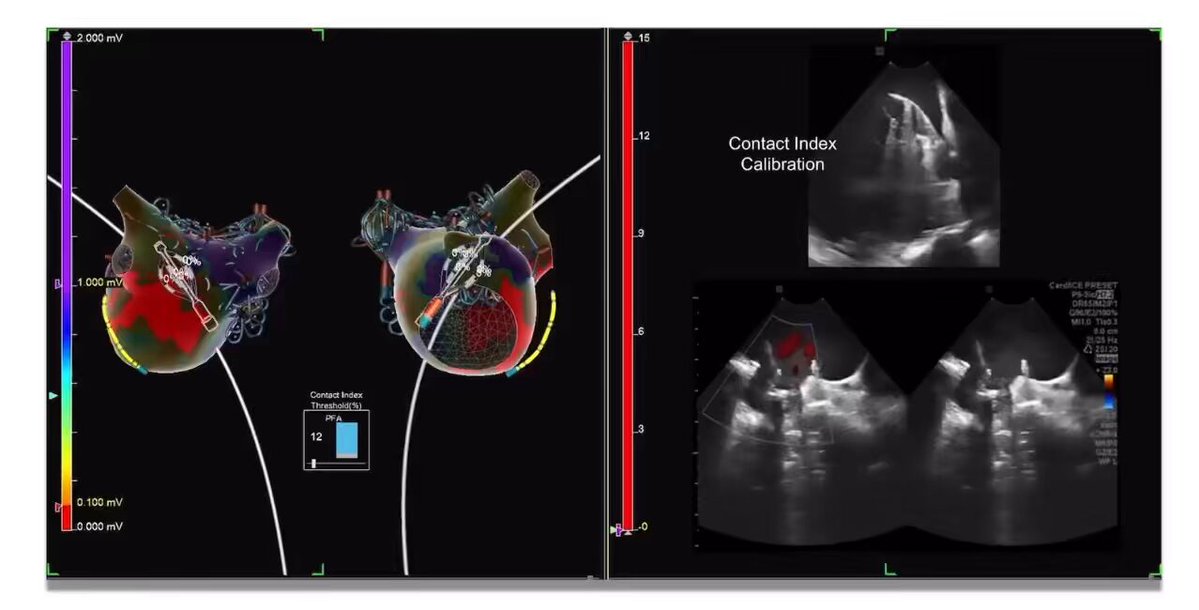

What actually "looks good" on ICE: #ViewFlex Left Atrial imaging @EPS_PDX Training @MRazminia Sponsored @AbbottCardio Complemented #EnSiteX PFA Visualization & Contact Index software. A post PFA induced tachycardia, entrained at downstream electrogram, with long upstream…